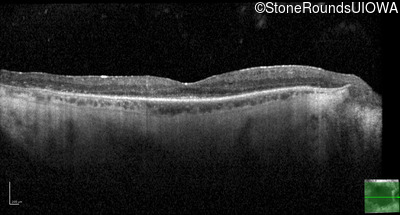

Optical Coherence Tomography - Right - 20/25 -1

Exemplar / OCT Stack